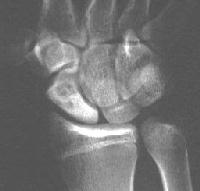

Clinical Example: Scaphoid fracture with total avascular necrosis similar to Preiser's disease

One of the problems with scaphoid fractures is ischemia of the proximal fracture fragment resulting in delayed union, nonunion or irretrievable avascular necrosis. In this case, ischemic changes involving the entire scaphoid are documented following a scaphoid fracture due to minimal trauma. This progressed with cystic changes and AVN on MRI. The patient had persistent pronounced wrist stiffness and pain. As pointed out to me by Dr. Lawrence Schneider (thanks!), this is technically not true Preiser's, for the fracture preceded the AVN.